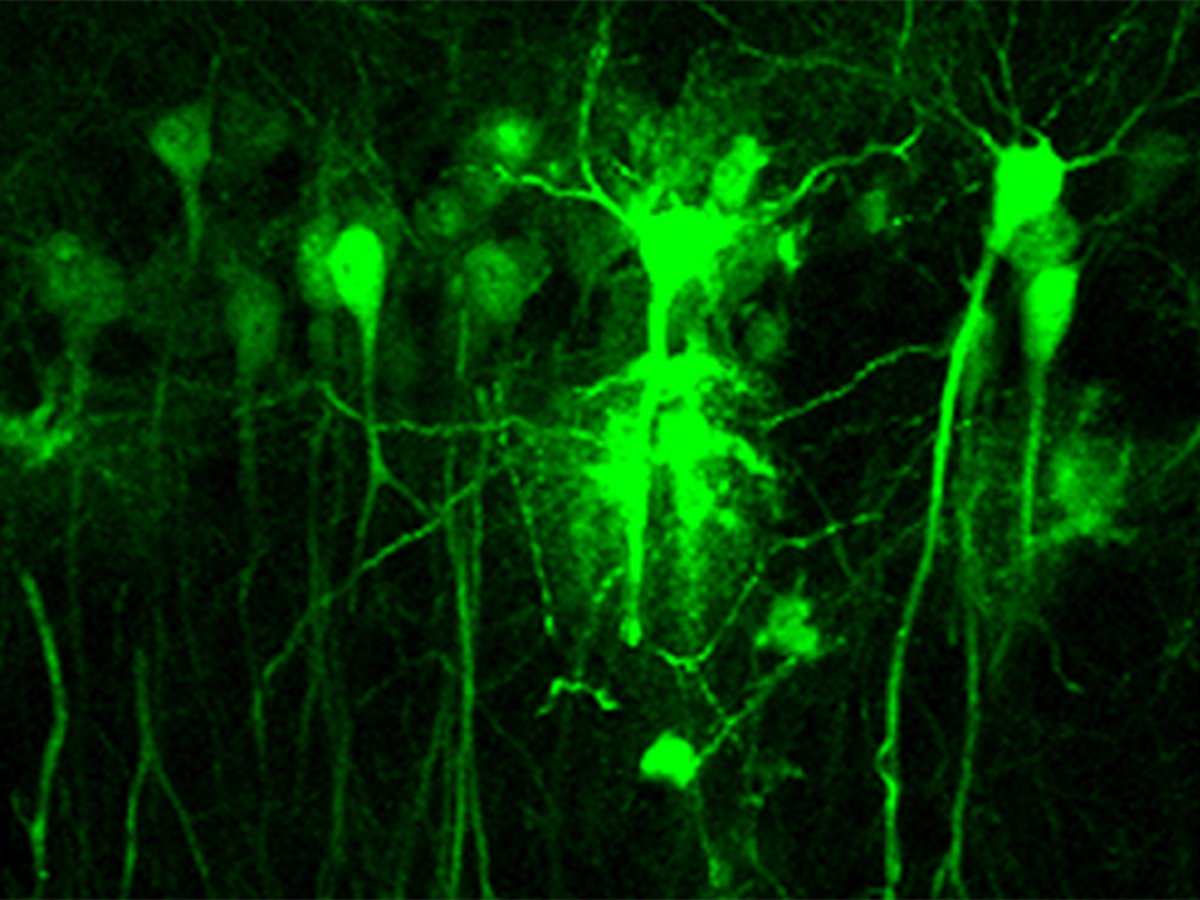

Neruonas

Un estudio liderado por investigadores del Consejo Superior de Investigaciones Científicas (CSIC) y el Centro Investigación Biomédica en Red Enfermedades Neurodegenerativas (Ciberned), en colaboración con la División de Neurociencias de la Universidad de Pablo Olavide (UPO), ha demostrado que es imprescindible la presencia del receptor dopaminérgico D2 en las neuronas del hipocampo para que la dopamina, uno de los principales neurotransmisores cerebrales, pueda modular los cambios sinápticos responsables de la adquisición y la consolidación de la memoria.

En la adquisición y la consolidación de la memoria está implicado el hipocampo mediante cambios plásticos en las sinapsis neuronales que almacenan la información recibida de otros núcleos y del exterior. "Hasta el momento se sabía que la dopamina era capaz de modular estos cambios, aunque se desconocían los mecanismos neuronales involucrados. En trabajos previos de laboratorio se había demostrado la importancia del receptor D1 en la memoria espacial y la plasticidad sináptica, pero quedaba por desvelar la implicación del receptor D2", señala Rosario Moratalla, investigadora del CSIC en el Instituto Cajal.

Combinando el uso de un modelo genético de ausencia del receptor D2 con estrategias de manipulación genética, los investigadores han comprobado que la falta de este receptor reduce la plasticidad sináptica en el hipocampo.